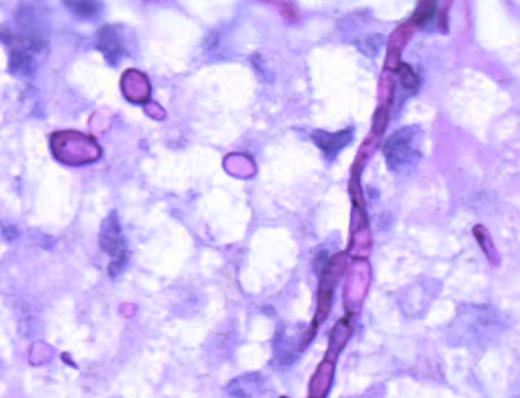

初令介绍,组织镜下发现肉芽肿,运用特殊染色及真菌免疫荧光等发现明确病源体类型,通过石蜡组织切片进行靶向高通量测序(TNGS(DNA)-META)锁定病原体,如烟曲霉、白色念珠菌、新型隐球菌等。这种从形态学疑诊到分子确认的全流程,充分展现了特殊感染多维诊断体系的综合优势。

这些病例成功诊断的核心引擎,正是新湘雅病理科着力构建的“形态学为基础-特殊染色初筛-免疫荧光精查-石蜡切片NGS测序确认”特殊感染多维诊断体系。该体系以传统的HE染色、特殊染色为基础,与新型的免疫荧光技术、前沿的石蜡切片TNGS(DNA)-META技术有机整合并互相印证,形成了强大的诊断合力。免疫荧光技术显著提高了病原体筛查敏感性,而TNGS(DNA)-META技术则实现了病原体的精准鉴别,多种技术优势互补,显著提升了诊断精准度。